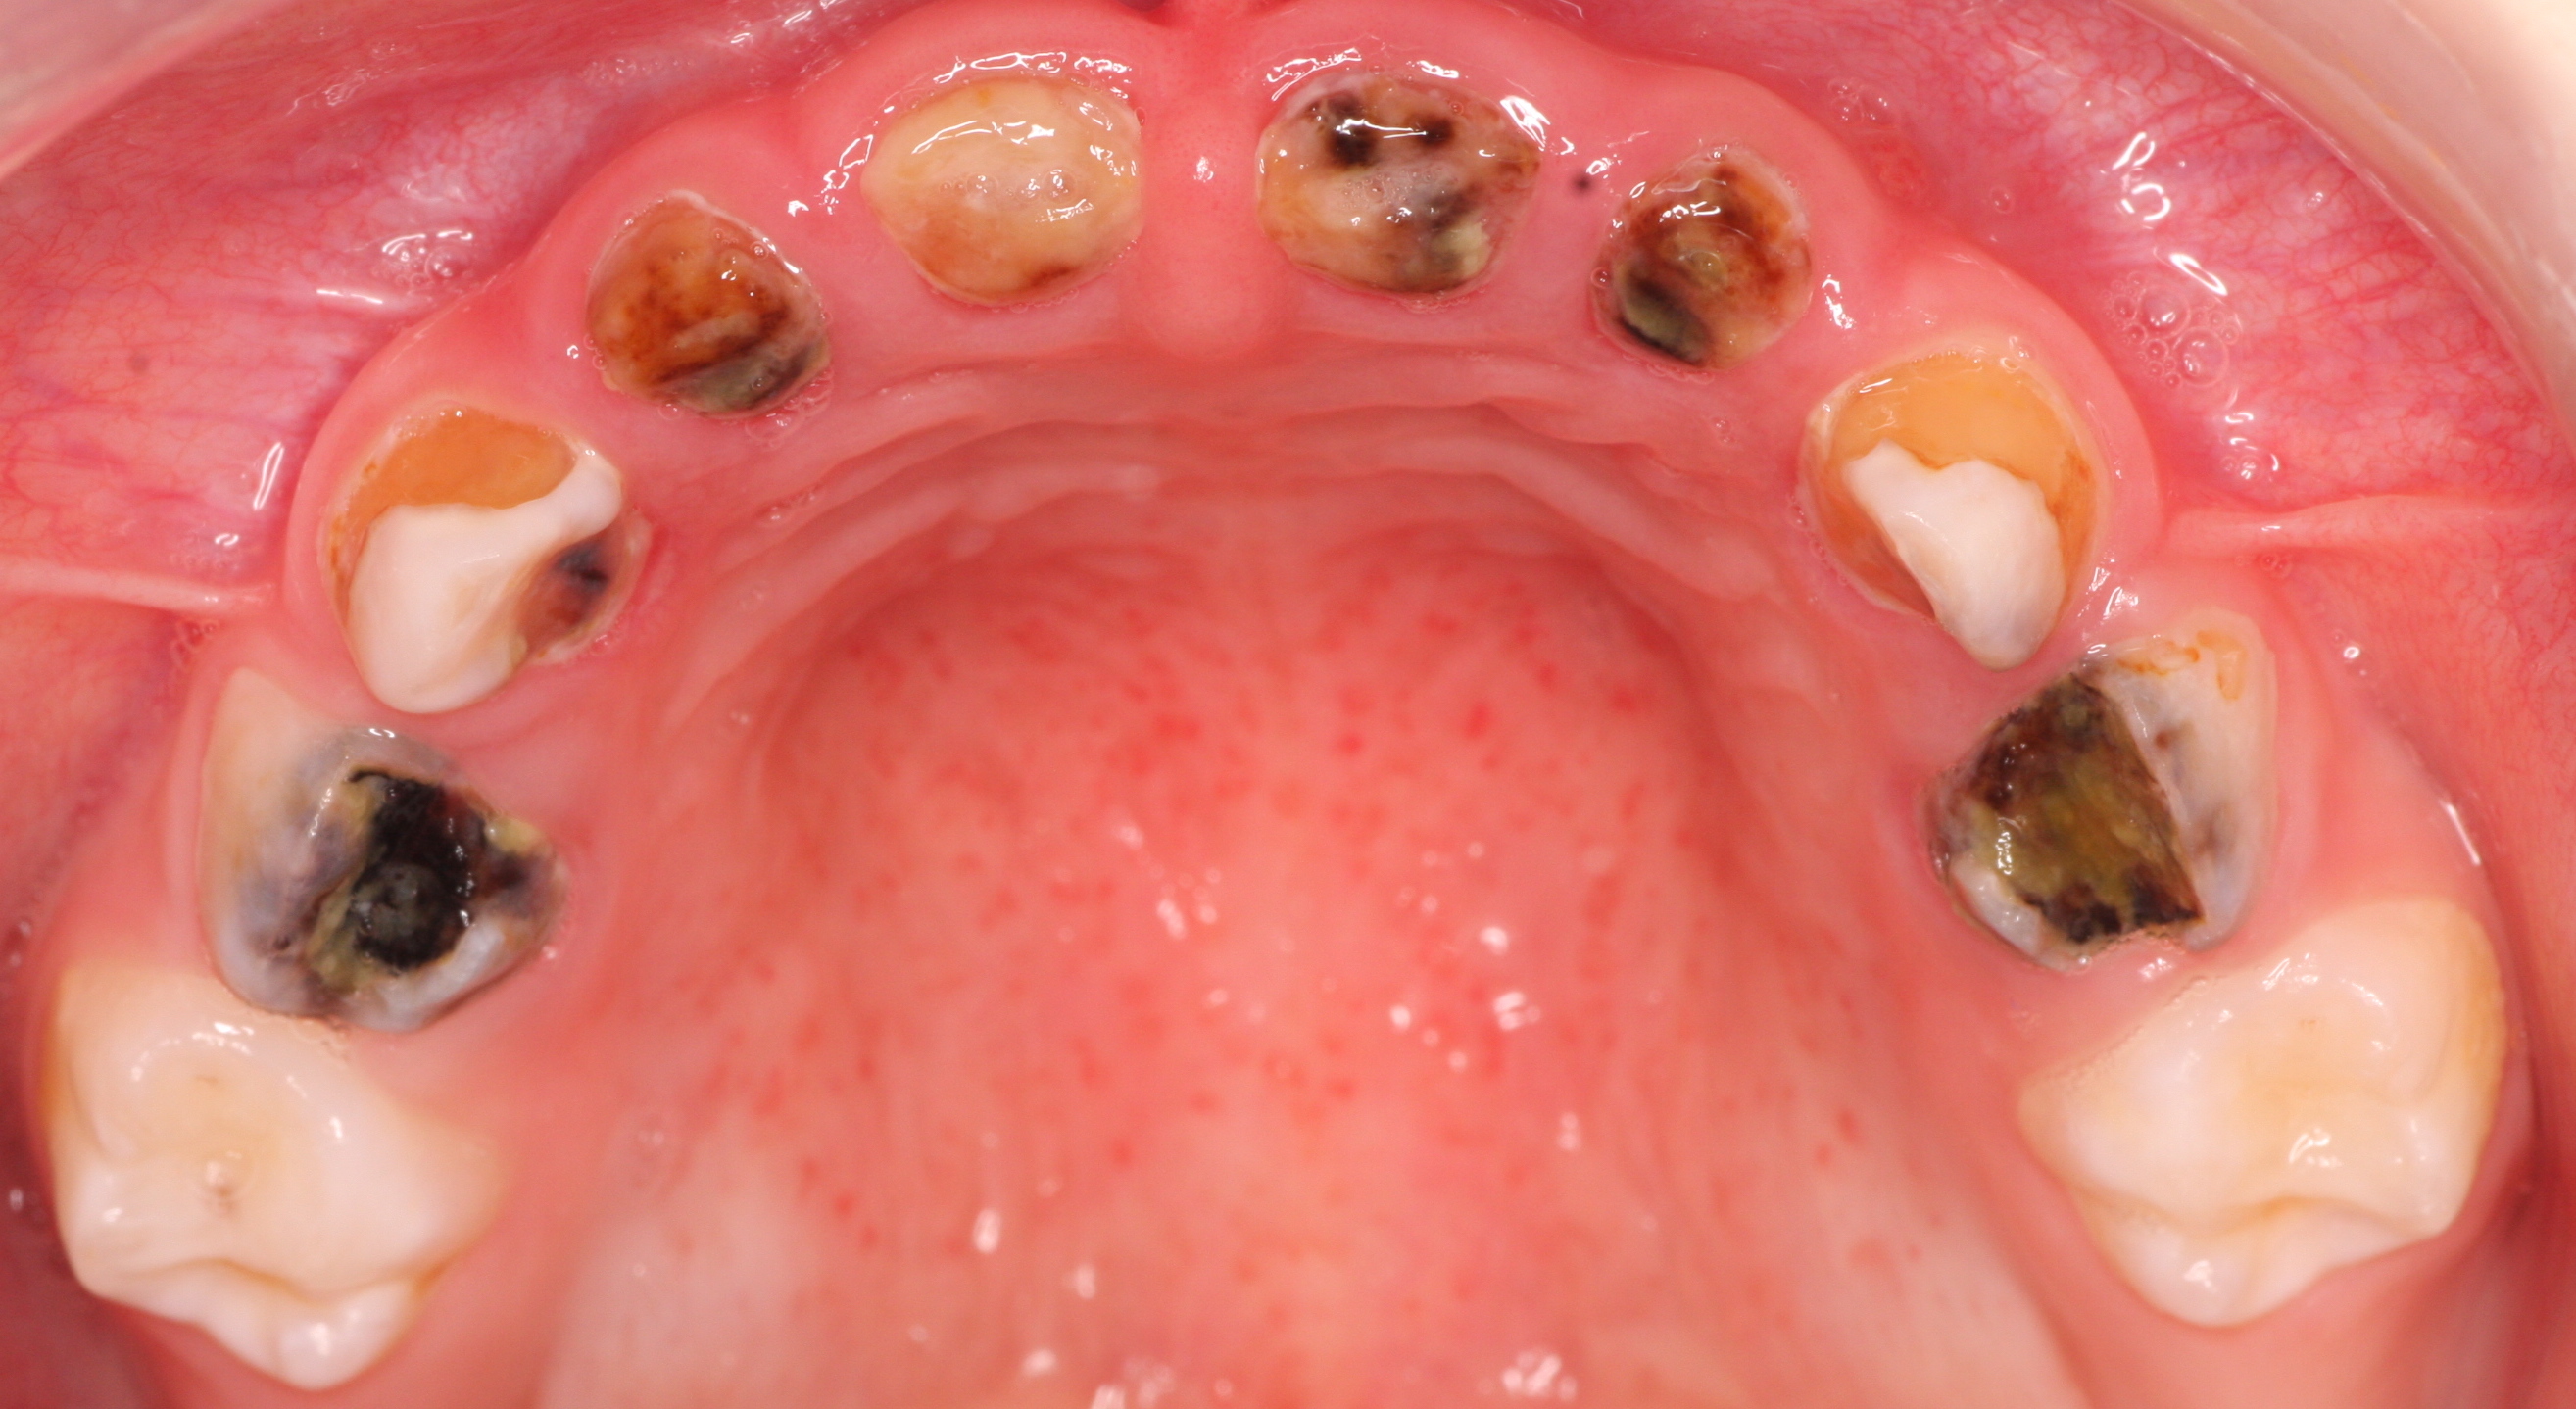

Trotz der insgesamt positiven Entwicklung der Mundgesundheit bei Kindern und Jugendlichen in Deutschland ist die Milchzahnkaries noch immer weit verbreitet. Insbesondere die frühkindliche Karies stellt mit einer Häufigkeit von ca. 14 Prozent bei den Dreijährigen ein erhebliches Gesundheitsproblem dar. In einem gemeinsamen Webinar, das am 14. Oktober live und kostenfrei im Internet übertragen wird, beleuchten Prof. Dr. Katrin Bekes und Daniel Grotzer die Frage, wie die Mundgesundheit der Kleinsten verbessert werden kann. In Vorbereitung auf das Online-Seminar, beantwortete Referentin Bekes im Interview mit Dental Tribune International ein paar Fragen zum Thema.

Prof. Dr. Bekes, was sind Ihrer Erfahrung nach die größten Faktoren, warum Milchzahnkaries noch immer ein weitverbreitetes Problem in Deutschland darstellt? Wie jede andere Kariesform ist auch die Milchzahnkaries ein multifaktoriell bedingter Prozess und als Folge eines zeitlich bestimmten Zusammenspiels von kariogenen Mikroorganismen mit vergärbaren Kohlenhydraten auf der Zahnoberfläche zu verstehen. Die Hauptursache für die Entwicklung solcher kariösen Prozesse im frühen Kindesalter liegt in einer häufigen Aufnahme zucker- und säurehaltiger Getränke und Nahrungsmittel. Die Gabe der Flasche erfolgt oft nicht nur aufgrund von Durst oder Hunger, sondern aus Langeweile und Unlust in den Ermüdungsphasen, als Einschlafhilfe, in nächtlichen Wachphasen oder zur Zwischenmahlzeit. Begünstigt wird der Prozess durch eine unzureichende Entfernung des Biofilms auf der Zahnoberfläche.

Was sind die Hauptlernziele, die die Zuschauer:innen aus Ihrem Webinar mitnehmen sollen? Die Teilnehmer:innen sollten fähig sein eine frühkindliche Karies zu diagnostizieren, deren Risikofaktoren zu kennen, Präventionskonzepte zu beschreiben und die verschiedenen Behandlungsmöglichkeiten der frühkindlichen Karies zu benennen.

Im Rahmen des Webinars „Starke Zähne für starke Kinder – Wie können wir die Mundgesundheit der Kleinsten verbessern?“, das am 14. Oktober, ab 17 Uhr live im Internet übertragen wird, geben Prof. Dr. Katrin Bekes und Daniel Grotzer, Senior Manager Professional and Scientific Relations DACH, einen Einblick in das klinische Bild und die Ätiologie der frühkindlichen Karies, sowie unterstützende Tipps hinsichtlich der Aufklärung und Beratung von Eltern mit ihren Kindern ab dem ersten Praxistermin. Alle Teilnehmer:innen haben die Möglichkeit, während der Übertragung per Chat Fragen an die Referentin zu stellen und sich im Anschluss durch das Beantworten eines Online-Fragebogens einen Fortbildungspunkt zu sichern. Registrieren Sie sich jetzt hier kostenfrei für das Oral-B-Webinar.